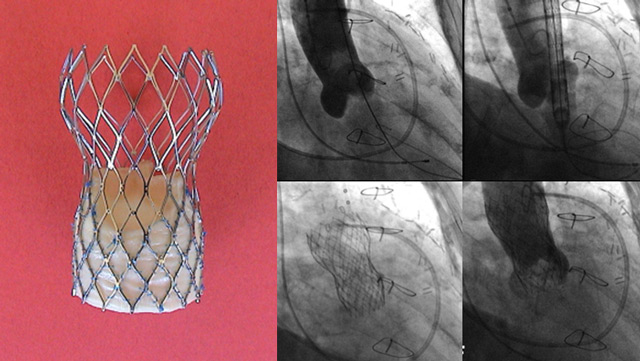

Transcatheter aortic valve implantation (TAVI)

Aortic stenosis (AS) is the most common valvular heart disease leading to intervention. It is characterized by progression from leaflet thickening and calcification to significant haemodynamic stenosis which results in disease-specific symptoms and physical limitations as well as poor prognosis and impaired quality of life if...